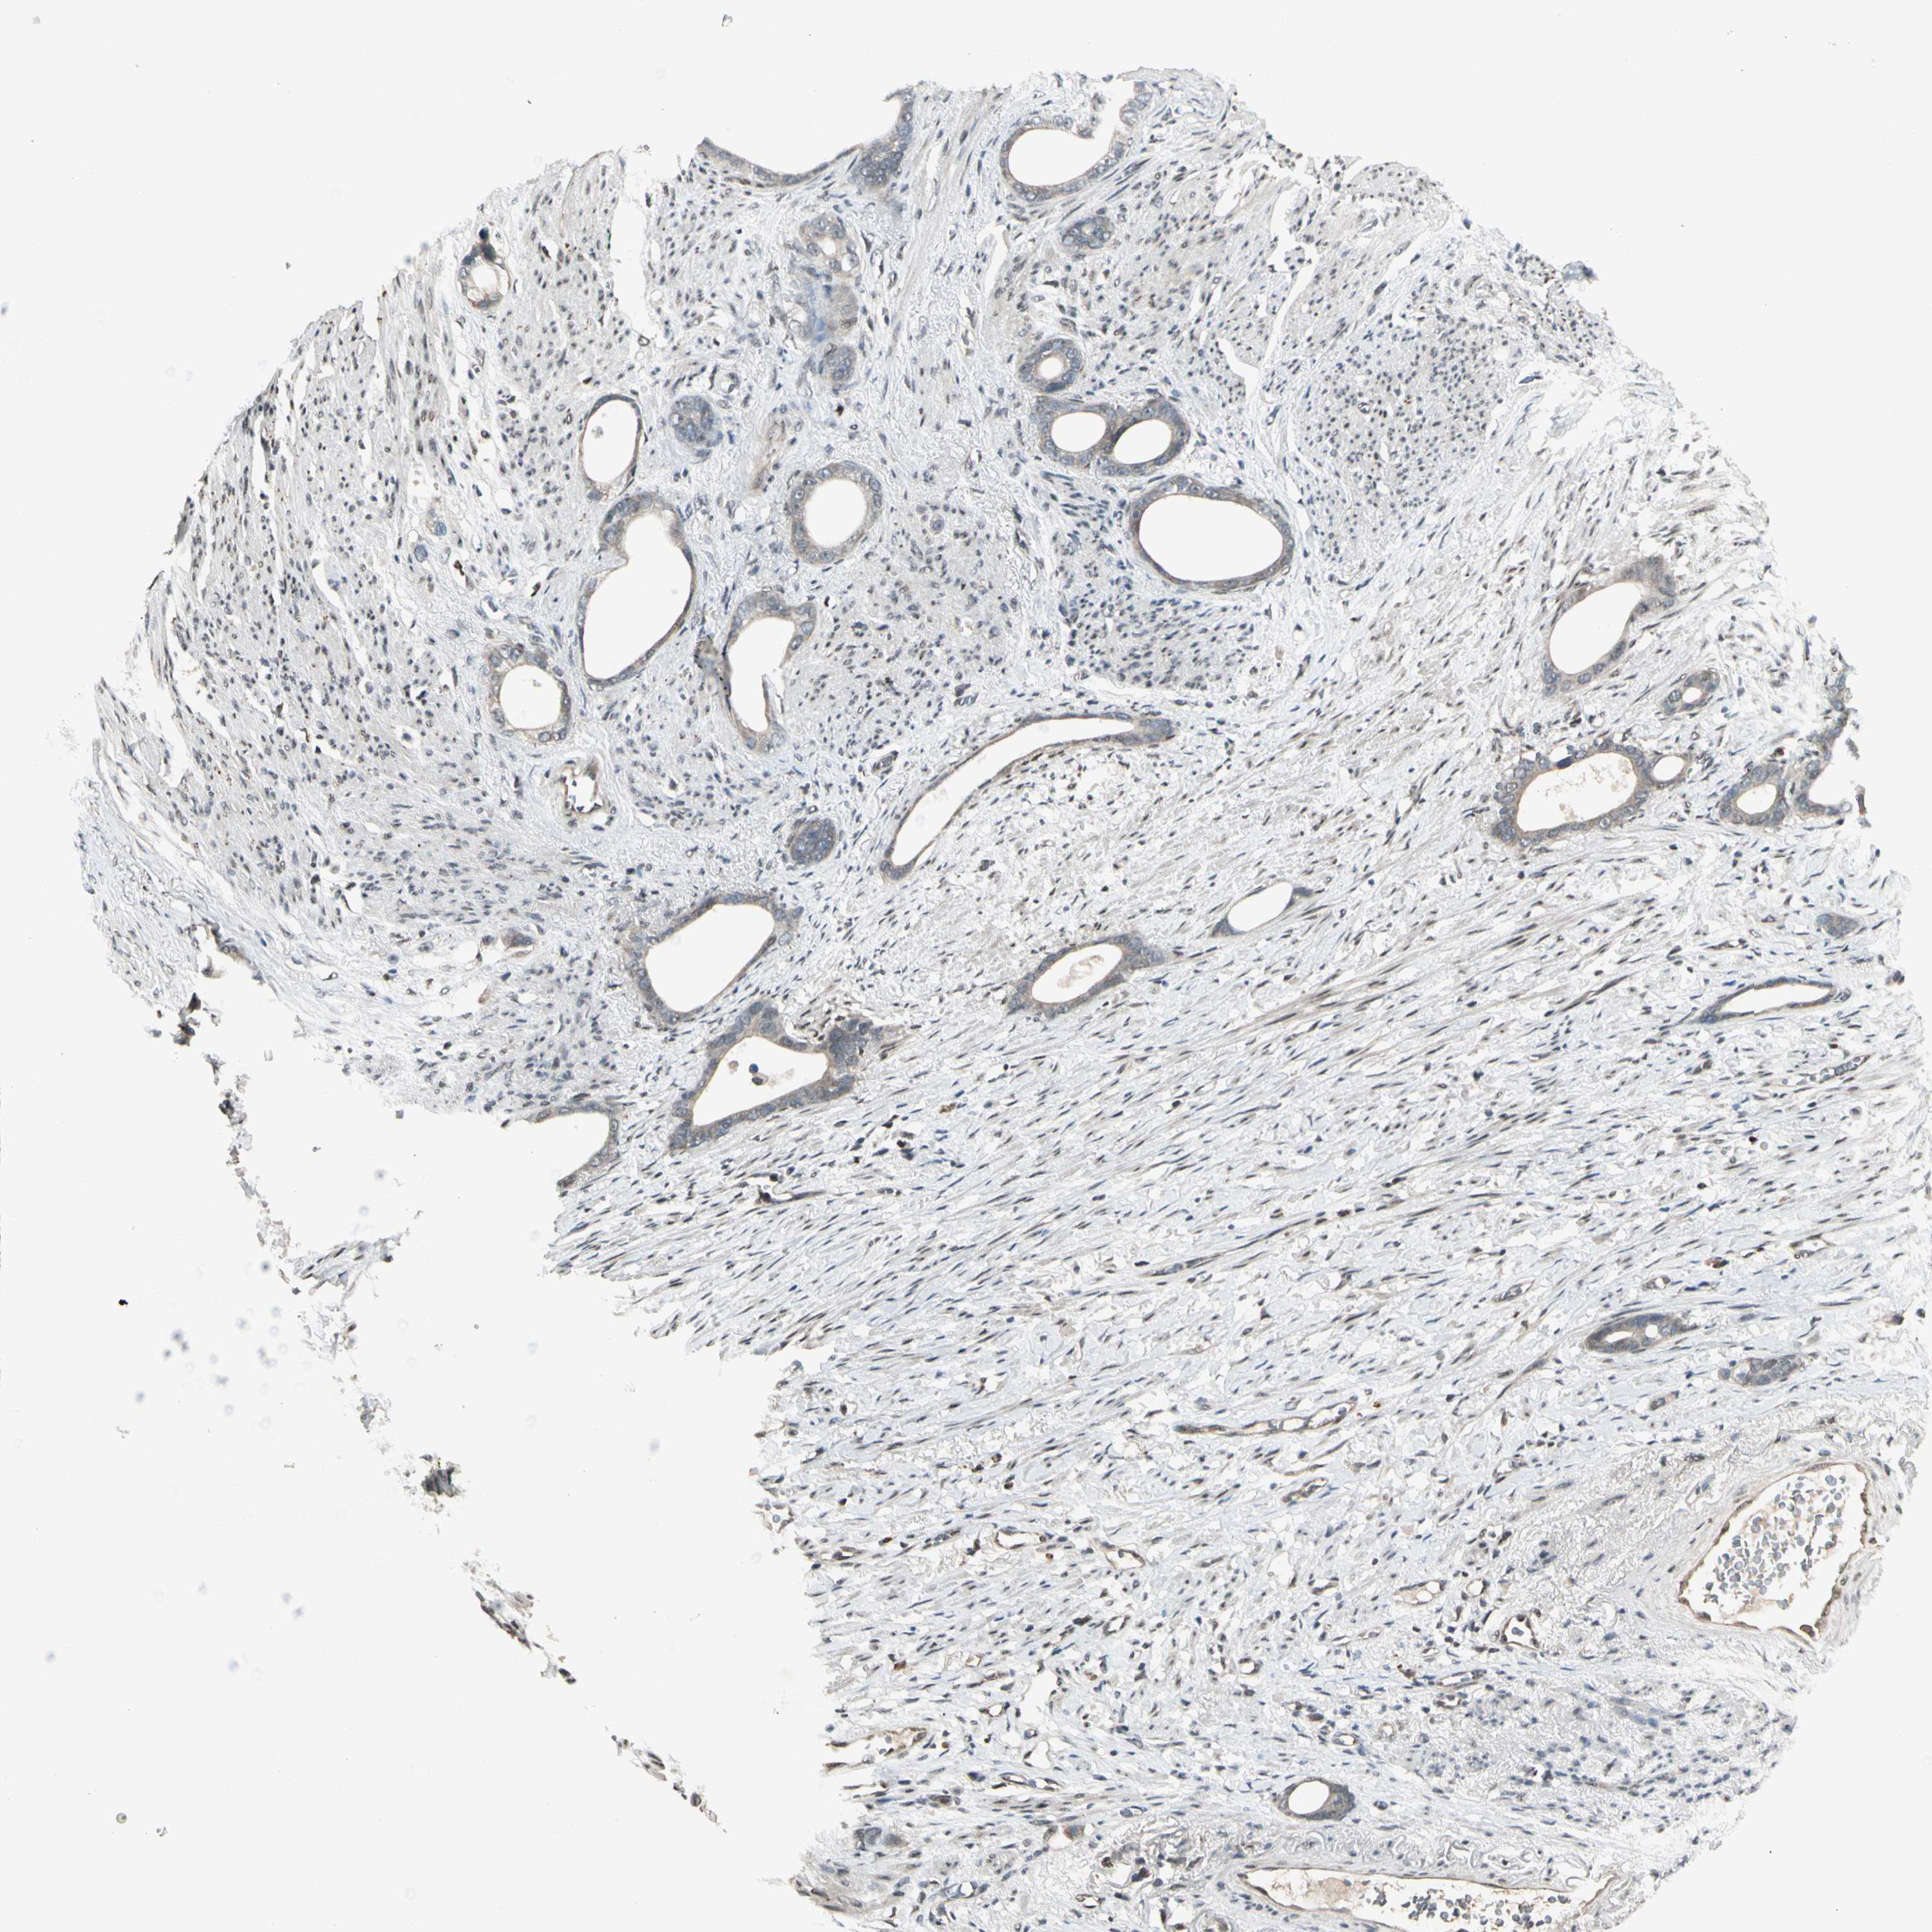

STOMACH CANCER - Protein expressioni

A mouse-over function shows sample information and annotation data. Click on an image to view it in a full screen mode. Samples can be filtered based on level of antibody staining by selecting one or several of the following categories: high, medium, low and not detected. The assay and annotation is described here.

Note that samples used for immunohistochemistry by the Human Protein Atlas do not correspond to samples in the TCGA dataset.

Antibody stainingi

Antibody staining in the annotated cell types in the current human tissue is reported as not detected, low, medium, or high, based on conventional immunohistochemistry profiling in selected tissues. This score is based on the combination of the staining intensity and fraction of stained cells.

Each image is clickable and will lead to virtual microscopy that enables deeper exploration of all samples and also displays staining intensity scores, fraction scores and subcellular localization as well as patient and tissue information for each sample.

Antibody HPA007990

Staining

High

Medium

Low

Not detected

Intensity

Strong

Moderate

Weak

Negative

Quantity

>75%

75%-25%

<25%

None

Location

Nuclear

Cytoplasmic/membranous

Cytoplasmic/membranous,nuclear

Adenocarcinoma, NOS